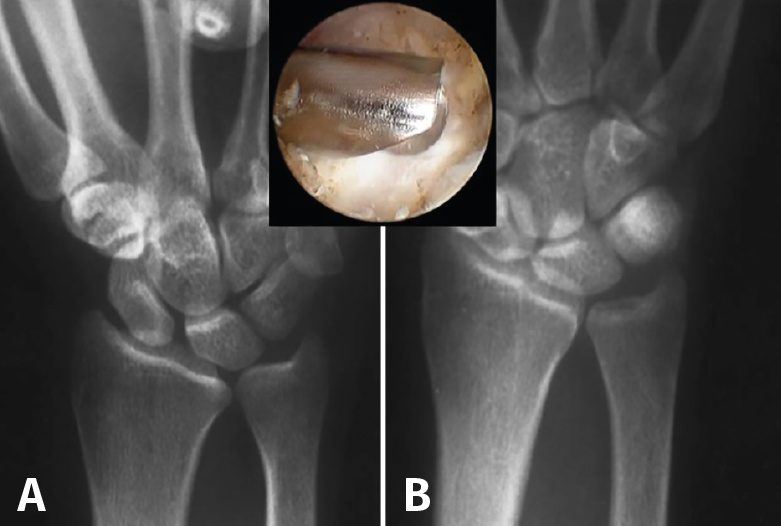

La alternativa más popular a la OAC es la resección parcial del cúbito distal o procedimiento de tipo wafer, con la que se han descrito también buenos resultados tanto de manera abierta (87% buenos o excelentes resultados) como de manera artroscópica (82% buenos o excelentes resultados)(11). Basado en los estudios sobre la modificación de las cargas cubitocarpianas de Palmer(1), Feldon(25) describió este procedimiento de manera abierta en 1992, consistente en resecar una fina oblea de la porción distal de la cabeza del cúbito. Presenta la ventaja, con respecto a la OAC, de que preserva la estructura y la biodinámica original de la ARCD y que no necesita implantar material de osteosíntesis. Prácticamente al mismo tiempo, Buterbaugh(26) describió la técnica de manera artroscópica, que hoy en día es la de elección para realizar un wafer, basado en los mismos fundamentos que la técnica abierta pero añadiendo las ventajas de permitir una completa evaluación diagnóstica de la muñeca, minimizar el daño a la cápsula dorsal radiocarpiana y radiocubital, producir menor dolor postoperatorio y una más rápida recuperación, al permitir una movilización postoperatoria prácticamente inmediata (Figura 5).

Figura 5. A: muñeca con varianza cubital positiva; B: varianza corregida tras wafer artroscópico.